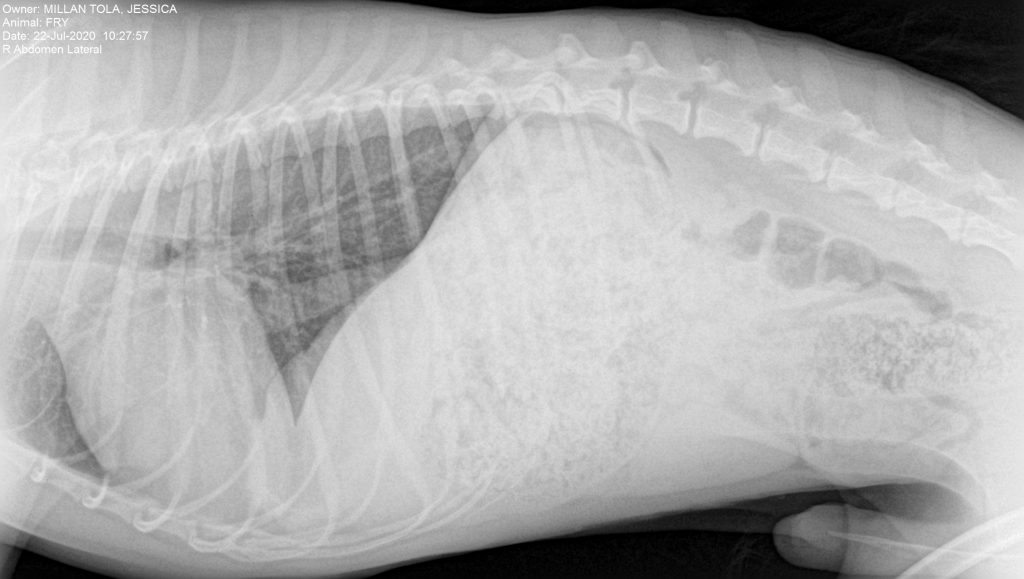

Fry es un macho de cuatro años de edad, que sufrió un accidente de tráfico. Fue atendido en un centro de urgencias y tras la estabilización solo detectaron una luxación de la cadera derecha.

En la radiografía lateral no observaron ninguna alteración destacable.

En la radiografía V-D de la pelvis se aprecia la luxación de la articulación coxofemoral del lado derecho.